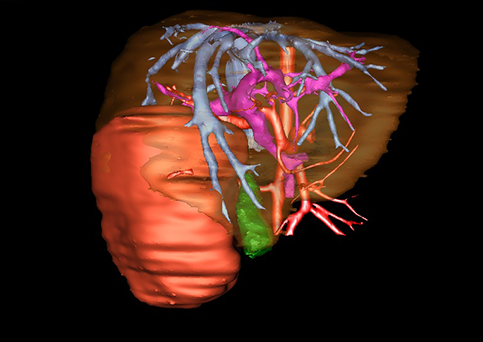

近年来由于数字医学的发展,基于可视化三维重建技术的计算机辅助手术系统极大推进了小儿肝脏肿瘤的精准手术的进步。可以立体透视肝脏解剖、精确掌握肝段的边界、精确测算肝段乃至任意血管所支配的功能体积、准确定位病灶及其与邻近血管的解剖关系,最终对不同手术方案进行比较、筛选和优化。因此,计算机辅助手术规划系统是实现精准肝切除的有力辅助工具,是未来数字外科、精准外科等21世纪外科新理念的重要技术支撑。

计算机辅助手术规划系统具有良好的操作可行性、计算准确性和三维显示效果,可半透明、交互式显示真实的肝内立体解剖关系和空间管道变异,准确计算肝内管道的直径、走行角度,两点间的垂直距离,和任意血管的支配或引流范围等传统二维影像无法获取的信息,有助于实施个体化手术,提高了手术的确定性、预见性和可控性。计算机辅助手术规划系统可直观显示预留肝脏的结构和功能,并可通过虚拟切割功能辅助术者对手术方案进行蹄选和优化,系统评估手术风险和制定对策,改变了部分二维规划的术式和切除范围,使部分二维规划认为不能切除的患者成功手术,提高了手术的根治性、安全性和病变的可切除性,更加符合精准肝脏外科的术前规划要求。详见第11章。

随着计算机技术及影像检查技术的不断发展,以精确的术前影像学和功能评估、精细的手术操作为核心的精准肝切除技术日益受到重视。基于数字医学的计算机辅助手术技术(computer-assisted surgery,CAS)则是实现肝脏精准手术操作的基础。计算机辅助手术系统(CAS)可将术前二维(two dimensional,2D)的CT/MRI影像数据进行三维(three dimensional,3D)重建,建立个体化的肝脏三维解剖模型,清晰显示肝脏内脉管系统的走行及解剖关系,还原病灶与其周围脉管结构的立体解剖构象,准确地对病变进行定位、定性和评估,制定合理、定量的手术方案,实施个体化的肝脏血管取舍分配方案及实施精准肝脏手术。一般认为CAS包括:创建虚拟的患者的图像;患者图像的分析与深度处理;诊断、手术前规划、手术步骤的模拟;术中实时导航。应用本技术后,由于可以更清晰地看出肿瘤的界限,特别是根据肝血管的显影,判断出肿瘤与门静脉及肝静脉的关系以在手术前较准确地估计出手术成功切除的可行性。以往部分根据普通强化CT判断无法手术的病例而被评估为可以成功切除并手术成功。

图23:肝中叶肿瘤二维CT图像